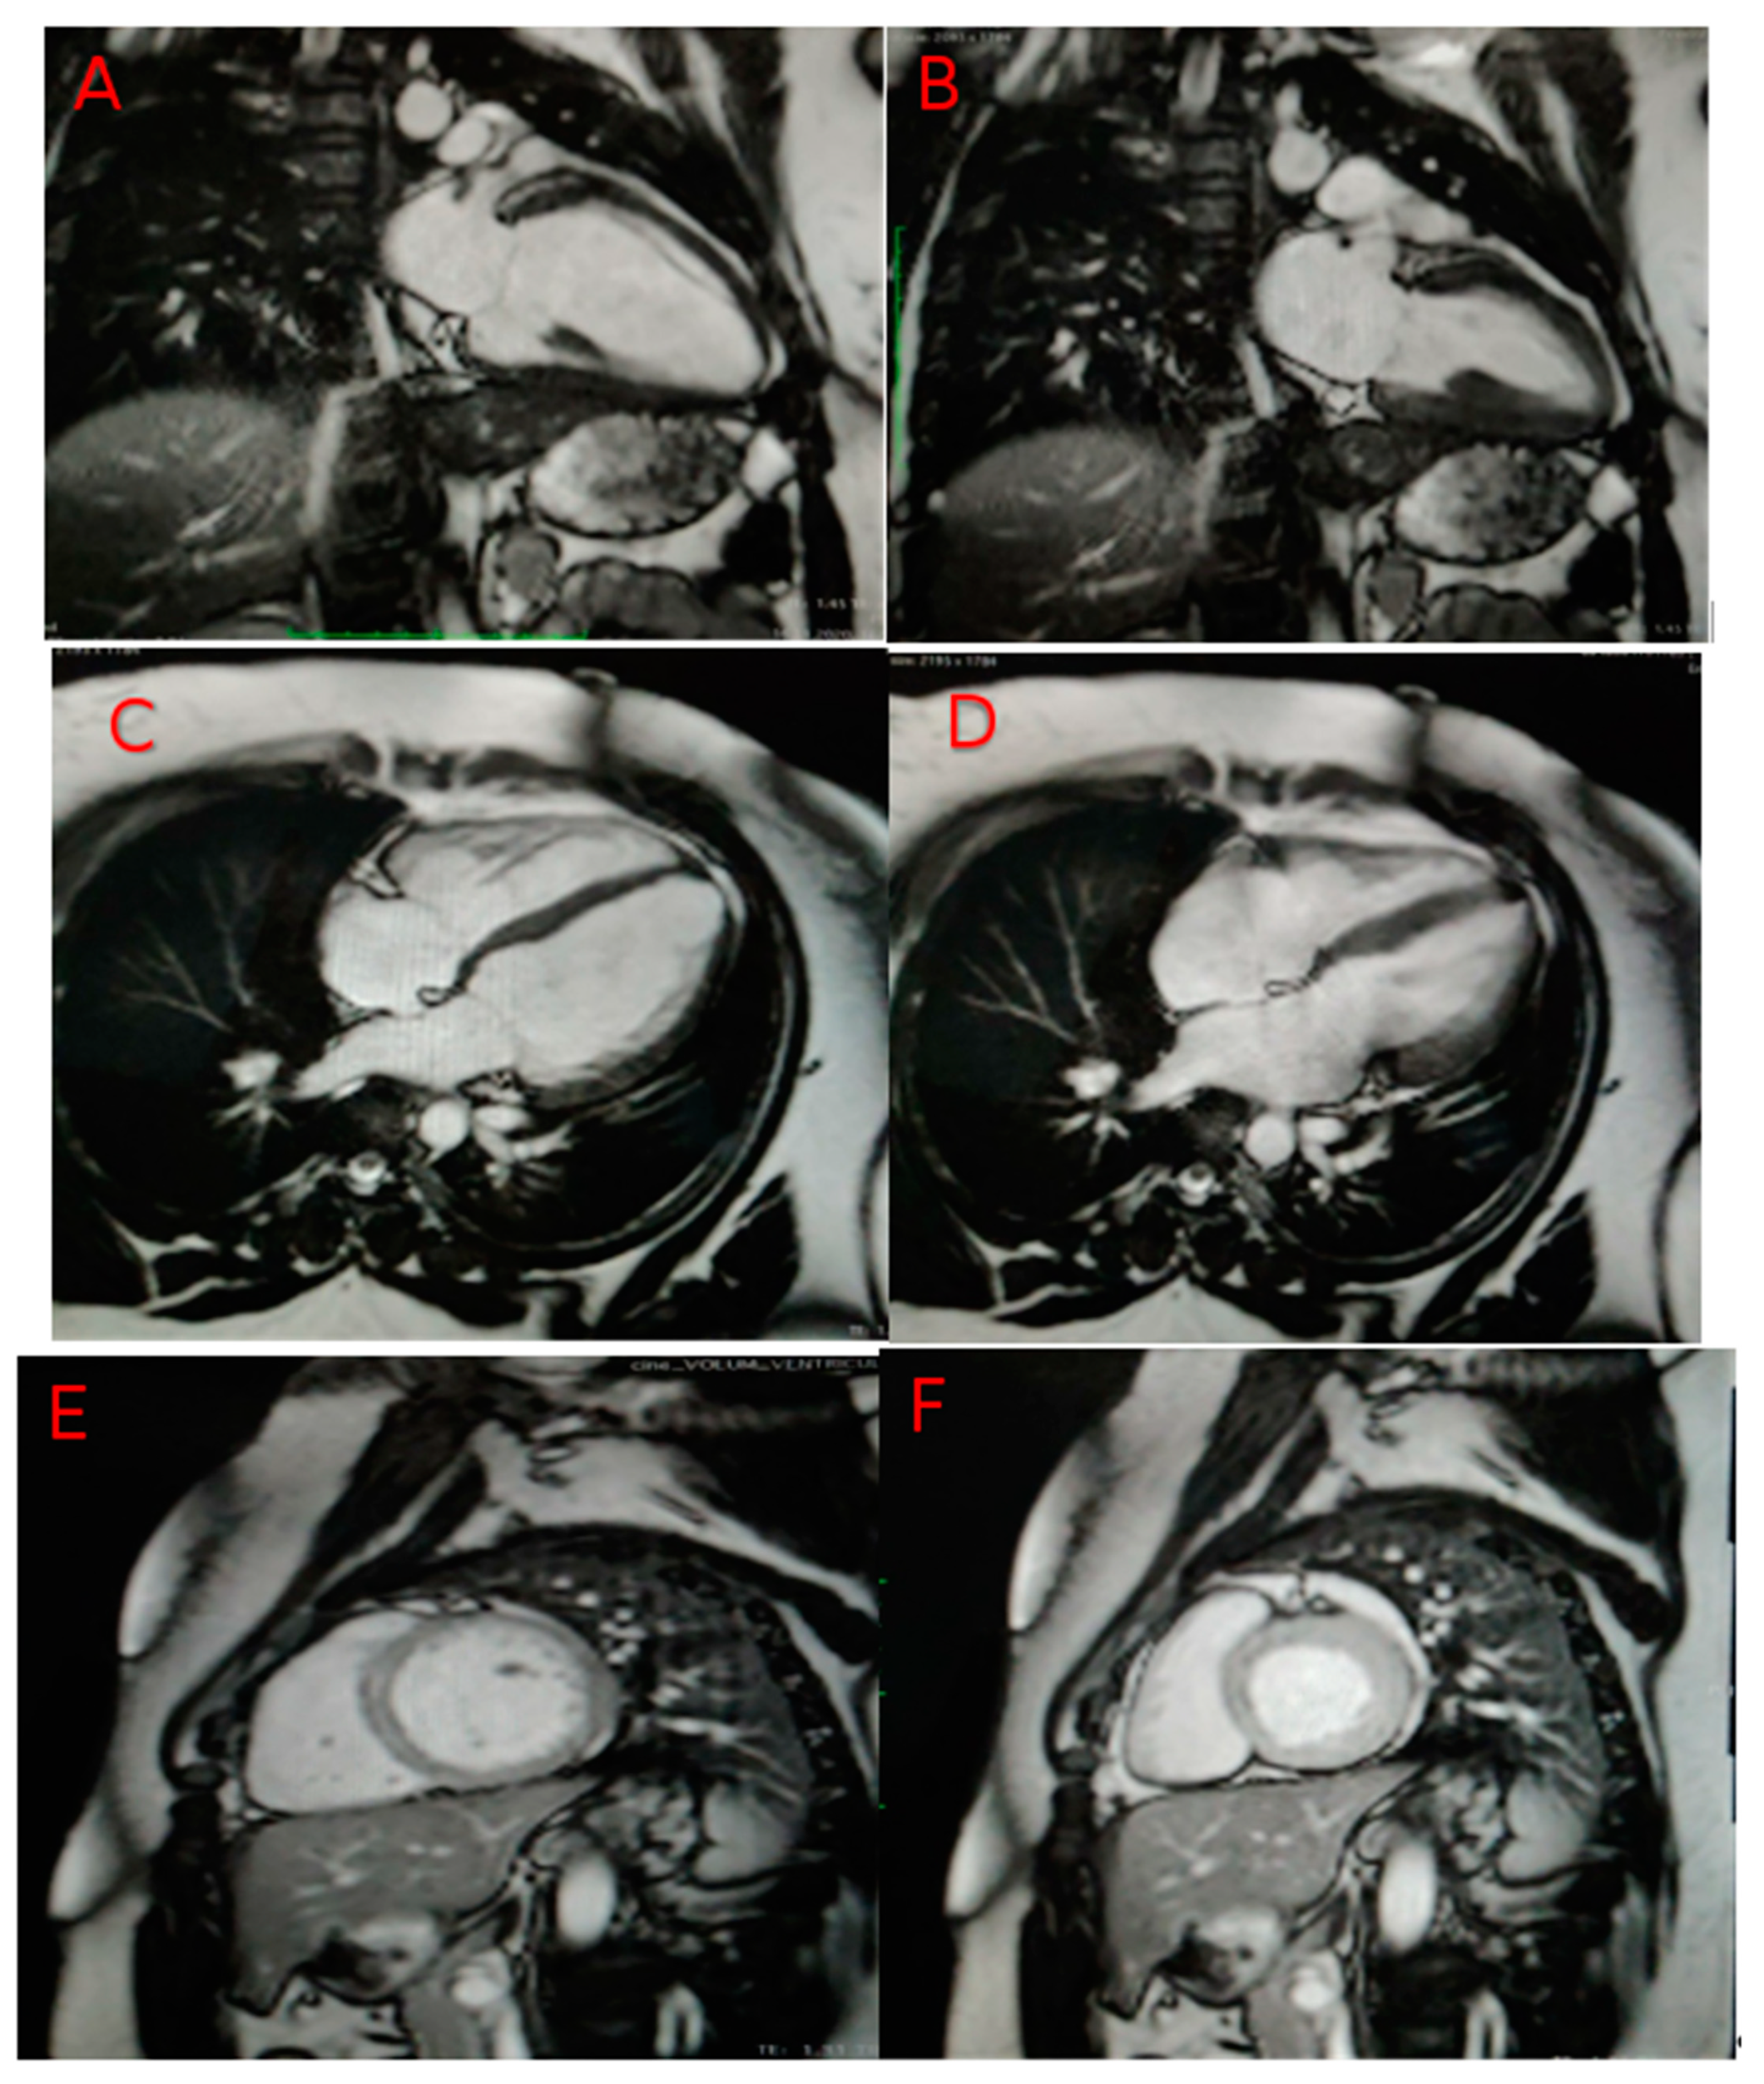

2. Case Presentation